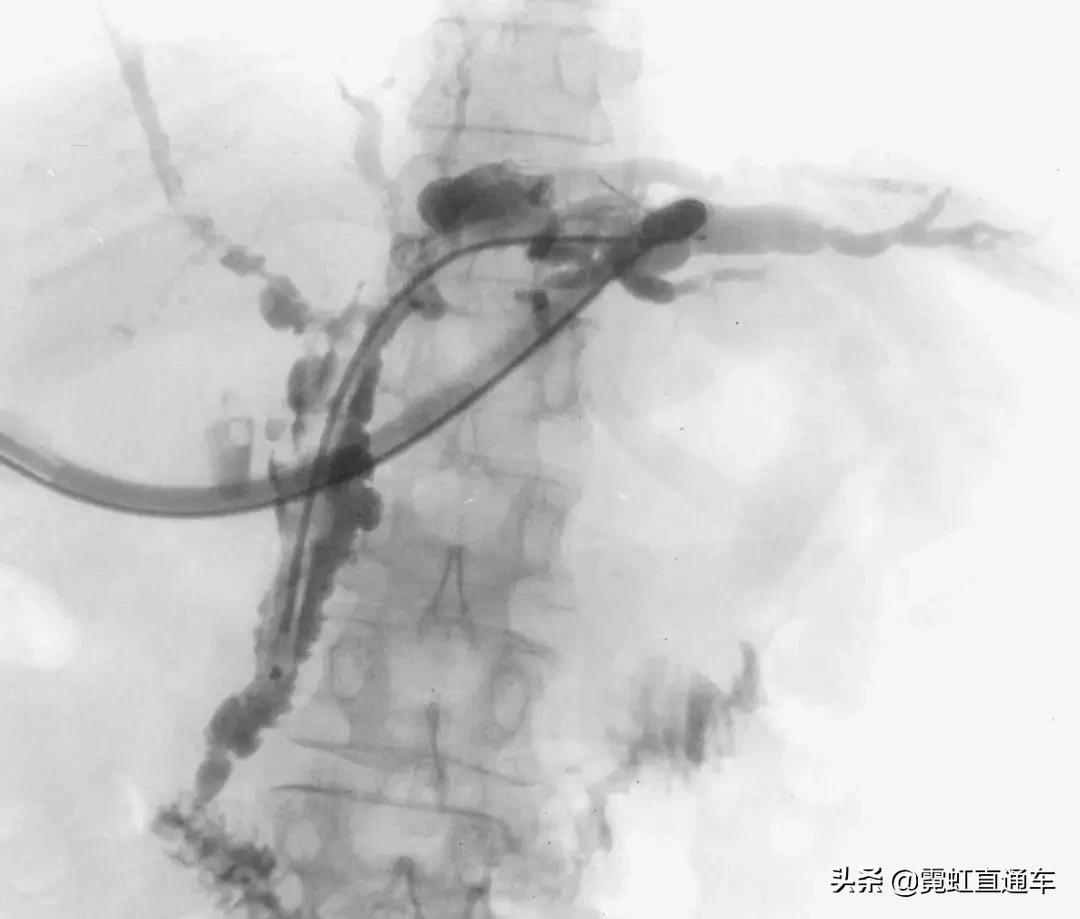

A.胆道影像学检查

1)特异性胆管征象

2)非特异性胆管征象

ERCP:胆管狭窄与扩张交互,呈串珠状改变

多发短小狭窄,胆管环状受累

PTCD:胆管呈边缘不整羽毛状

ERC:胆管壁呈憩室样突出